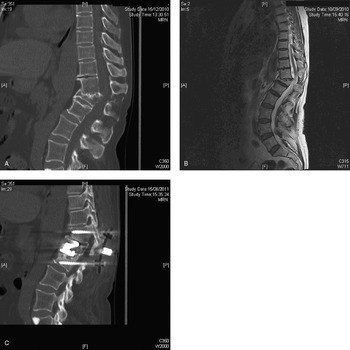

Traumatic Spinal Injury (Section 2) - Traumatic Brain and Spinal Cord Injury